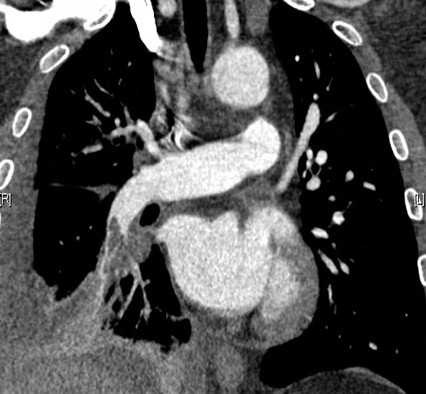

4、急诊检查:对于急性胸痛患者,可进行一次快速、非侵入式扫描,就能诊断出是否有心脏疾病、肺栓塞或者主动脉夹层三大主要导致胸痛的最致命性原因。对于外伤患者,通过短短10秒钟的扫描和先进的后处理软件能够对脏器的损伤和骨折做出及时诊断,为临床抢救赢得了时间,而且也节约了检查费用。